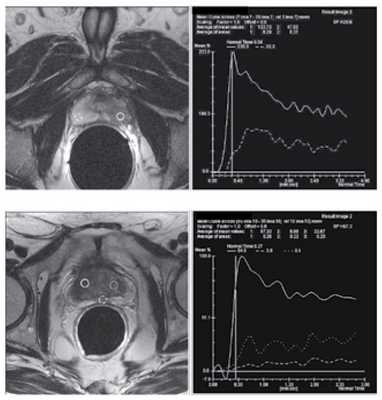

Магнитно-резонансная томография с динамическим контрастированием

Метод позволяет определить подозрительные участки с наличием опухолевых клеток по скорости накопления в них контрастного препарата. Для методики характерен очень высокий пик накопления в участках опухоли за счет высокой ее васкуляризации и неоангиогенеза. В норме накопление парамагнетика происходит в течение 60 секунд. При РПЖ этот показатель снижается до 20-30 секунд (рисунок 7).

Рисунок 7. МРТ с динамическим контрастированием

Магнитно-резонансная спектроскопия

Известно, что злокачественные клетки имеют очень низкий метаболизм цитрата, но высокое содержание холина и креатина. Поэтому показатель соотношения холин-креатин/цитрат может способствовать диагностике рака. МР-спектроскопия уже давно существует на рынке, и последние работы говорят о том, что ее действительно можно использовать как дополнительный метод в диагностике РПЖ (рисунок 6).

Рисунок 6. МР-спектроскопия при РПЖ